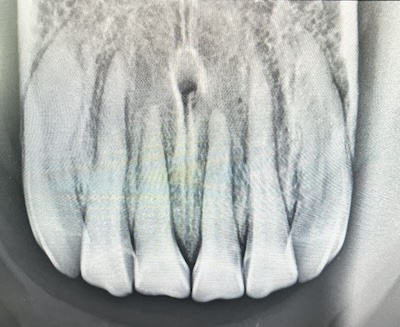

Hos ældre heste ser vi hyppigere tandforandringer, herunder diastemer og resorptive lidelser som Equine Odontoclastic Tooth Resorption and Hypercementosis (EOTRH).

Disse tilstande kan være smertefulde, men udvikler sig ofte stille. Ved mistanke kan røntgenundersøgelse af fortænderne være afgørende for at sikre korrekt diagnose og behandling.